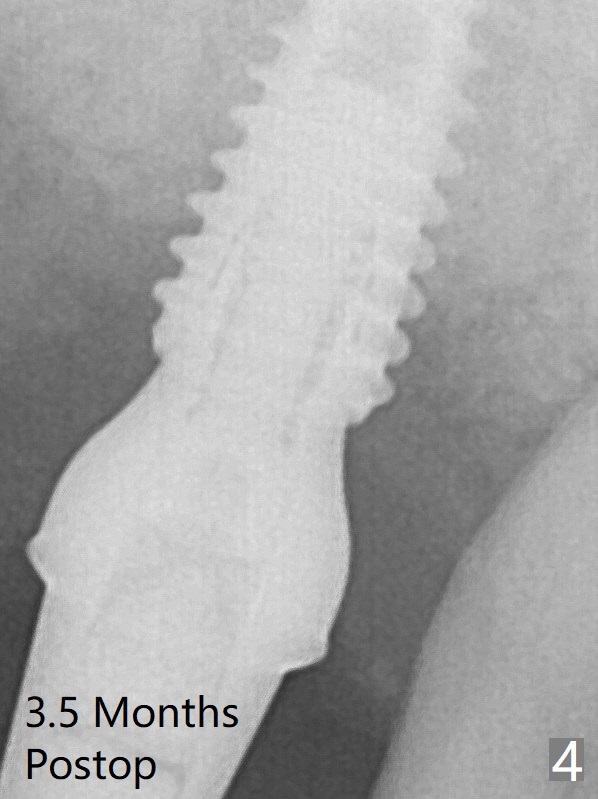

Sinus lift is accomplished with RT3 and autogenous bone prior to placement of a 4.5x8.5 mm implant (Fig.3). Because of flapless surgery and tight and long gingiva, bone graft around the coronal end of the implant is intentionally not placed. A 5.5x5(4) mm abutment is immediately placed for an immediate provisional. The provisional dislodges 3.5 months postop (Fig.4); impression is taken. The patient reports hot sensitivity and pain after meal at the implant site (Fig.5). After removal of the implant crown/abutment, she feels better.